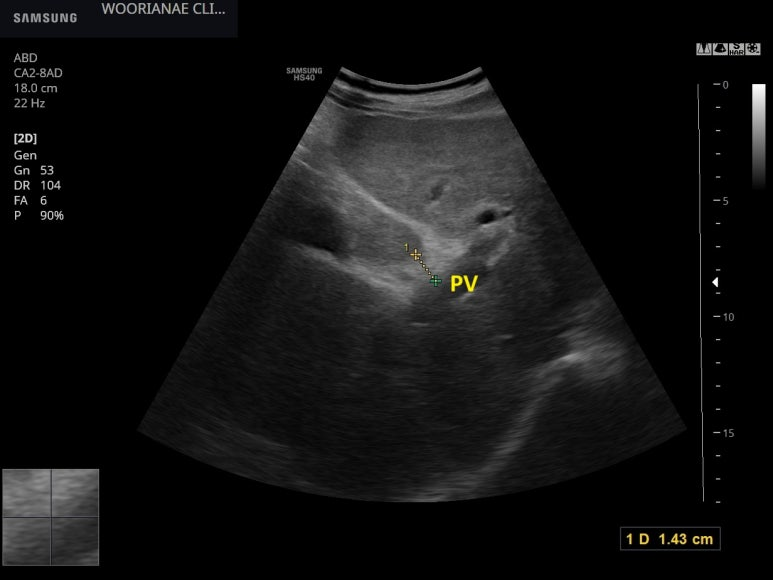

상기 환자 2주뒤 간암검진

fissure of ligamentum venosus 가 벌어지는 혹은 S1 미상엽이 커지는..

Periportal space가 넓어지는...

전반적인 표면의 물결과 같은 변화 (명확한 결절성 변화)

우엽이 표면도...

두드러지게 거친 간실질

4년전과 달리 <간경화> 로서 설명

초음파상 진행한 섬유화 혹은 간경화의 판단, 이행단계로서 흑백은 아니지만..